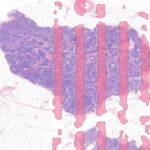

NIJMEGEN, Paesi Bassi–(BUSINESS WIRE)–Aiosyn, un’azienda che sviluppa software di patologia basati sull’intelligenza artificiale, ha lanciato il suo primo prodotto che aiuta i laboratori di patologia digitale nei settori della ricerca, della diagnostica e della farmaceutica a migliorare il processo di controllo di qualità (QC). AiosynQC è un algoritmo alimentato dall’intelligenza artificiale che analizza automaticamente gli artefatti più comuni che si verificano durante il processo pre-analitico eterogeneo.

L’algoritmo di AiosynQC è addestrato su vetrini colorati con ematossilina ed eosina (H&E). Il prodotto aiuta i laboratori a garantire che solo le immagini di alta qualità siano utilizzate da patologi, tecnici e ricercatori. Può contrassegnare i casi prima della presentazione al patologo, migliorando così l’efficienza del flusso di lavoro della patologia digitale, riducendo il tempo attualmente impiegato per verificare manualmente la presenza di artefatti nelle immagini di vetrini interi.